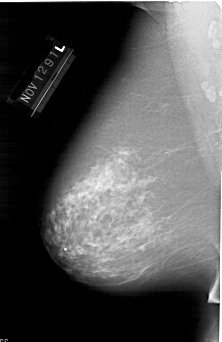

A_1648_1.LEFT_MLO

LEFT_MLO LINES 6481 PIXELS_PER_LINE 4201 BITS_PER_PIXEL 12 RESOLUTION 43.5 NON_OVERLAY